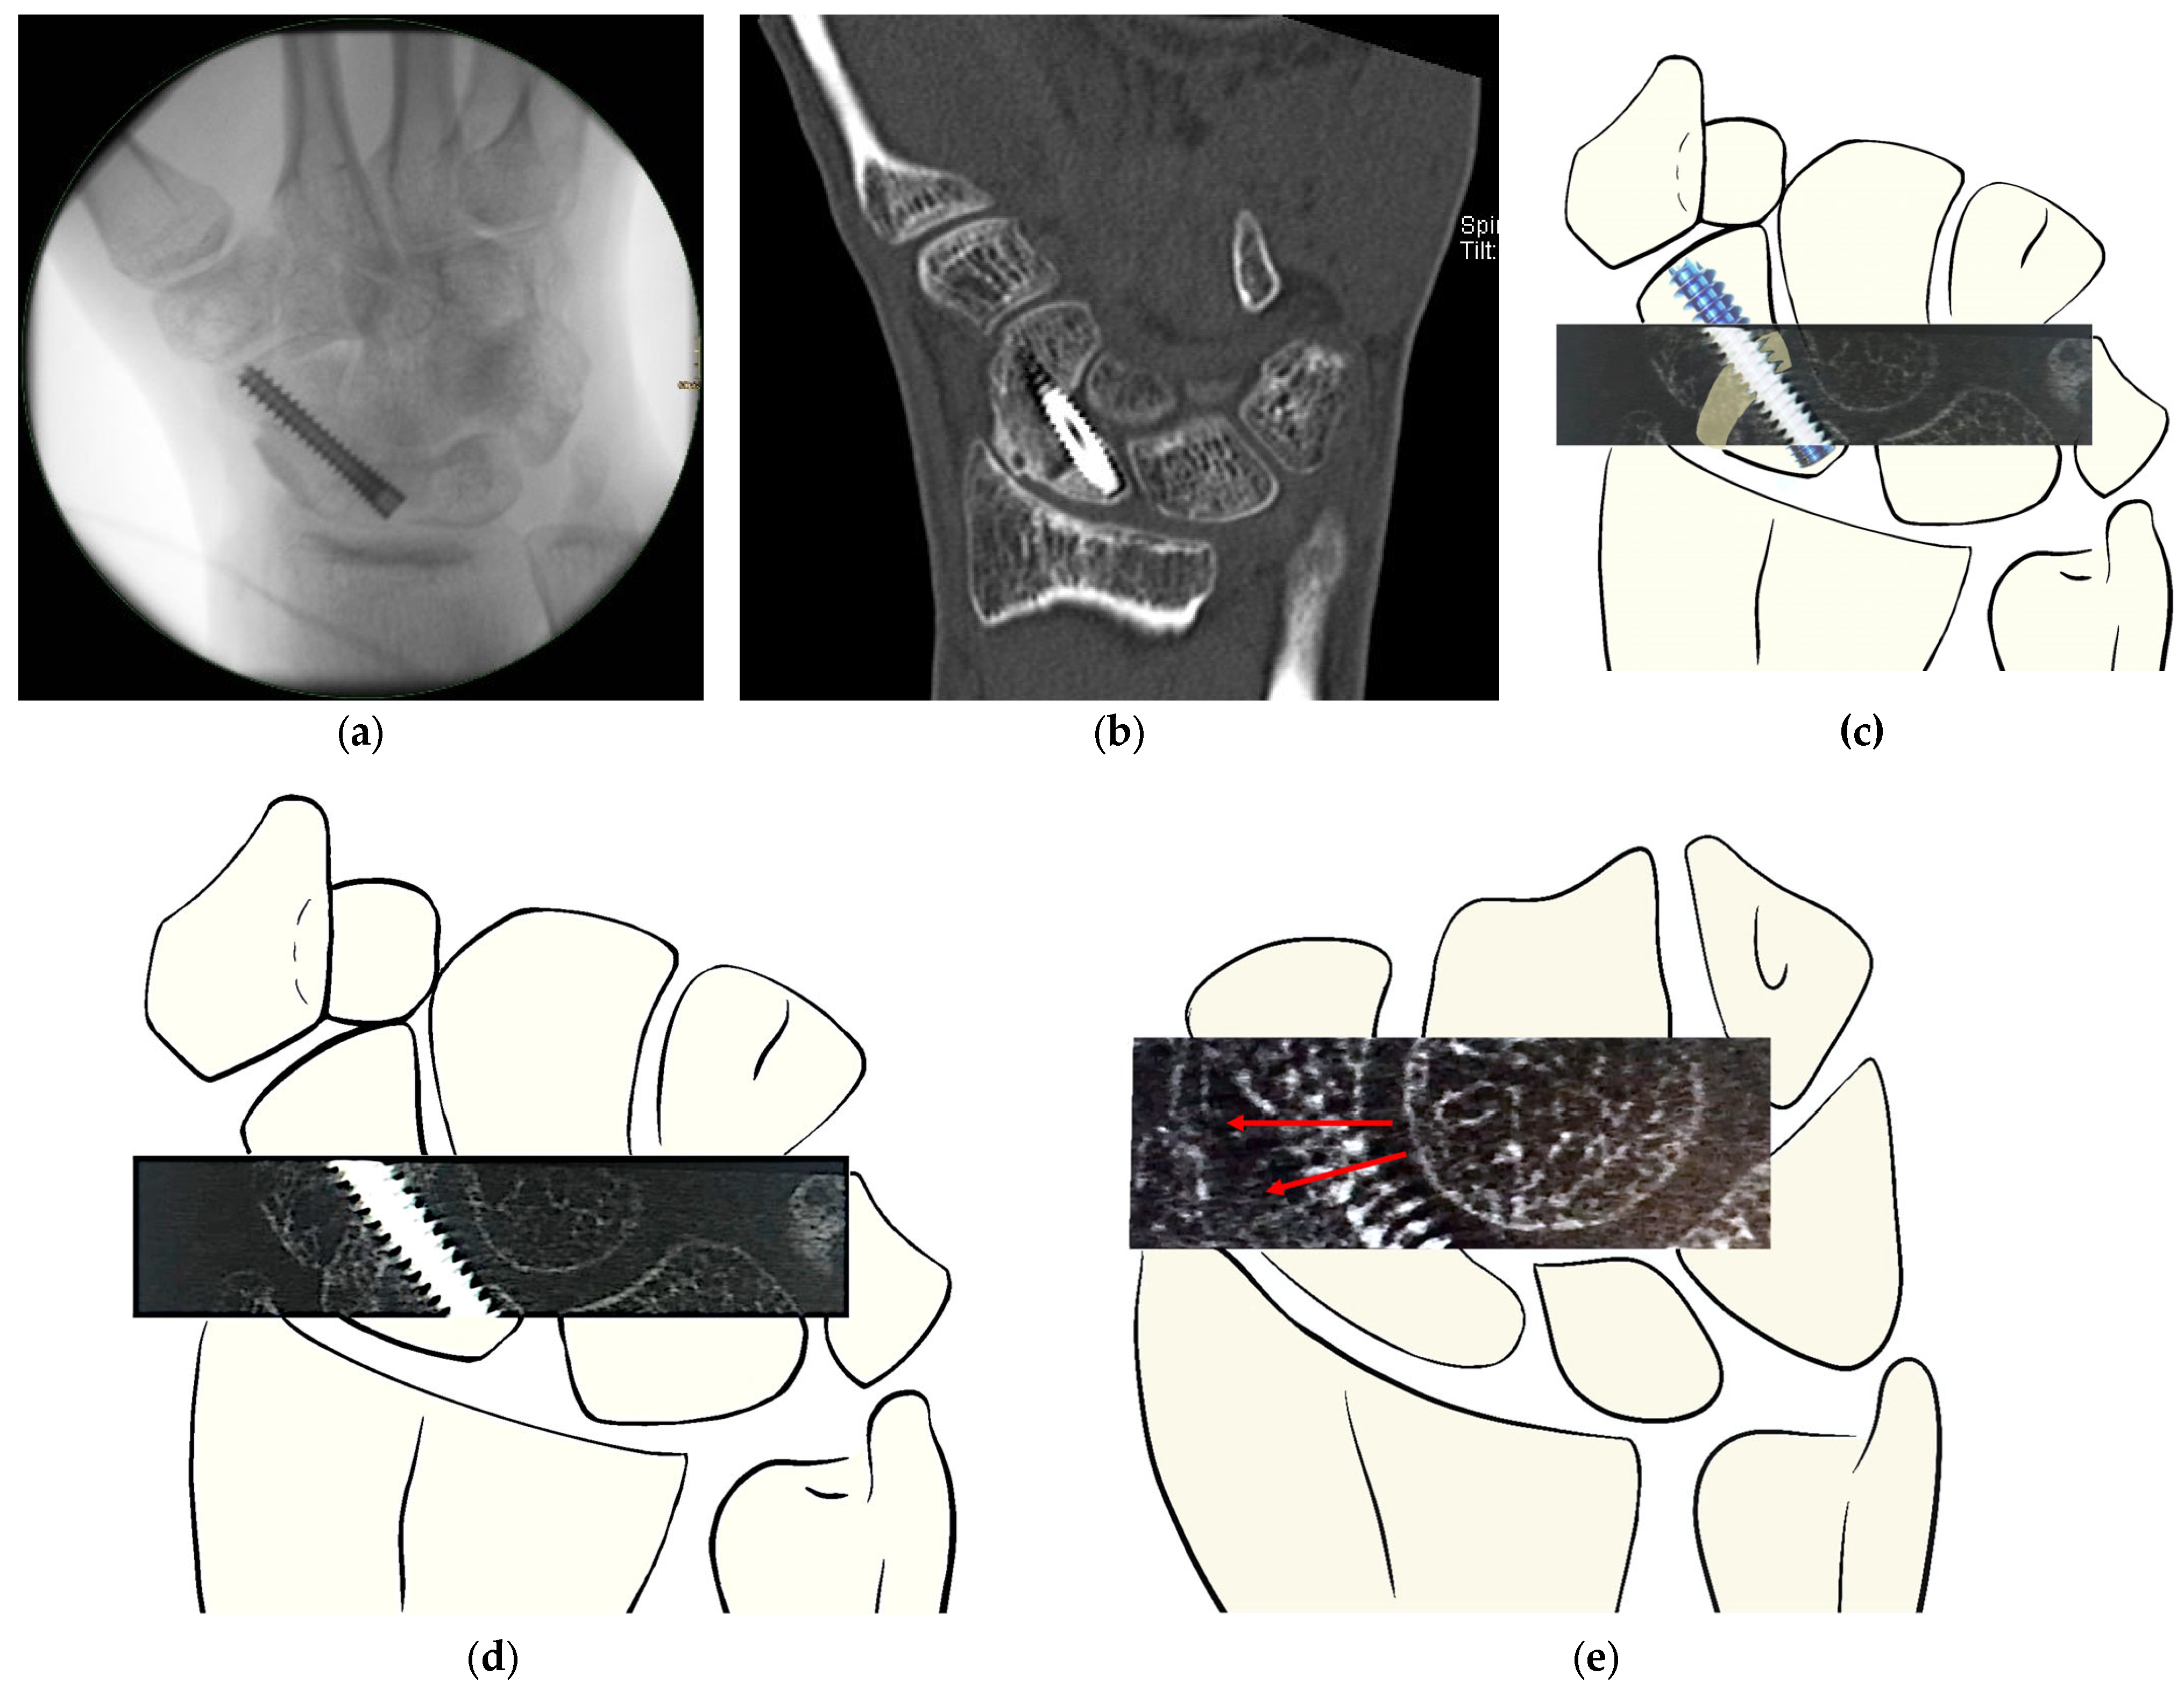

The two observers independently assessed bone consolidation at both the distal and proximal interfaces. For both HR-pQCT and MDCT, evaluations focused on the interface between the distal scaphoid pole and the iliac crest graft, as well as the interface between the graft and the proximal scaphoid pole. An example of the assessment method is illustrated in Figure 1.

Figure 1. Assessment of bone consolidation after revision surgery of scaphoid non-union with avascular iliac crest graft and percutaneous headless screw fixation. (a) Intraoperative imaging after iliac grafting and screw placement. (b) Post-operative MDCT scan at 6 weeks showing nearly complete healing at the distal interface and almost no bone consolidation at the proximal interface. (c) Schematic illustration of the HR-pQCT stack displaying the iliac graft positioning withing the scaphoid by S. Holzer. (d,e) Examples of obtained HR-pQCT scans of the same patient at 6 weeks after surgery, demonstrating trabecular structure present in the proximal and distal interfaces. (d) Display of well-distinguished ridges of the iliac graft, with clear trabecular structures, yet lacking bony bridging at the interfaces, suggesting resorption at the graft ridge. (e) Cross-section at a different scaphoid level; red arrow: display of blurry trabecular formation as described by Bevers et al. [22], a precursor to well-defined trabecular arches (schematic illustration by S. Holzer).